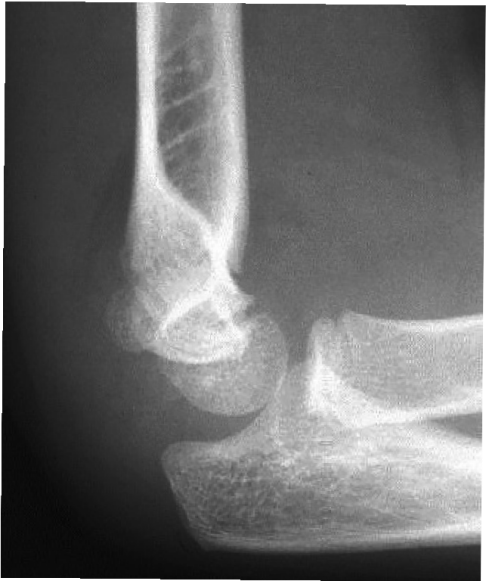

Fractures around the elbow

There are many ossification centres around the elbow appearing at different timesas the child matures. These ossification centres may look like fractures to the inexperienced eye. The acronym CRITOE/ CRMTOL is useful to remember the ossification centres and when they appear. The appearance of the ossification centres is summarised in the table and images below.

C | Capitellum | 1–2 years |

R | Radial head | 3–4 years |

I/M | Internal/medial epicondyle | 5–6 years |

T | Trochlea | 7–8 years |

O | Olecranon | 9–10 years |

E/L | External/lateral epicondyle | 11–12 years |

Supracondylar fractures

There is a weak spot above the humeral condyles at the level of the olecranon and coronoid fossae. Injuries here are typically FOOSH.

- X-rays: AP and lateral and a contralateral views of the elbow or both in cases of uncertainty. The Gartland Classification (Grade I–III) is used to grade these fractures.

III. Completely displaced fracture

Here there is a completely displaced fracture (See below: the anterior humeral line does not pass through the capitellum). There is a high risk of neurovascular injury (an orthopaedic emergency). These patients require urgent reduction and referral for operative management.